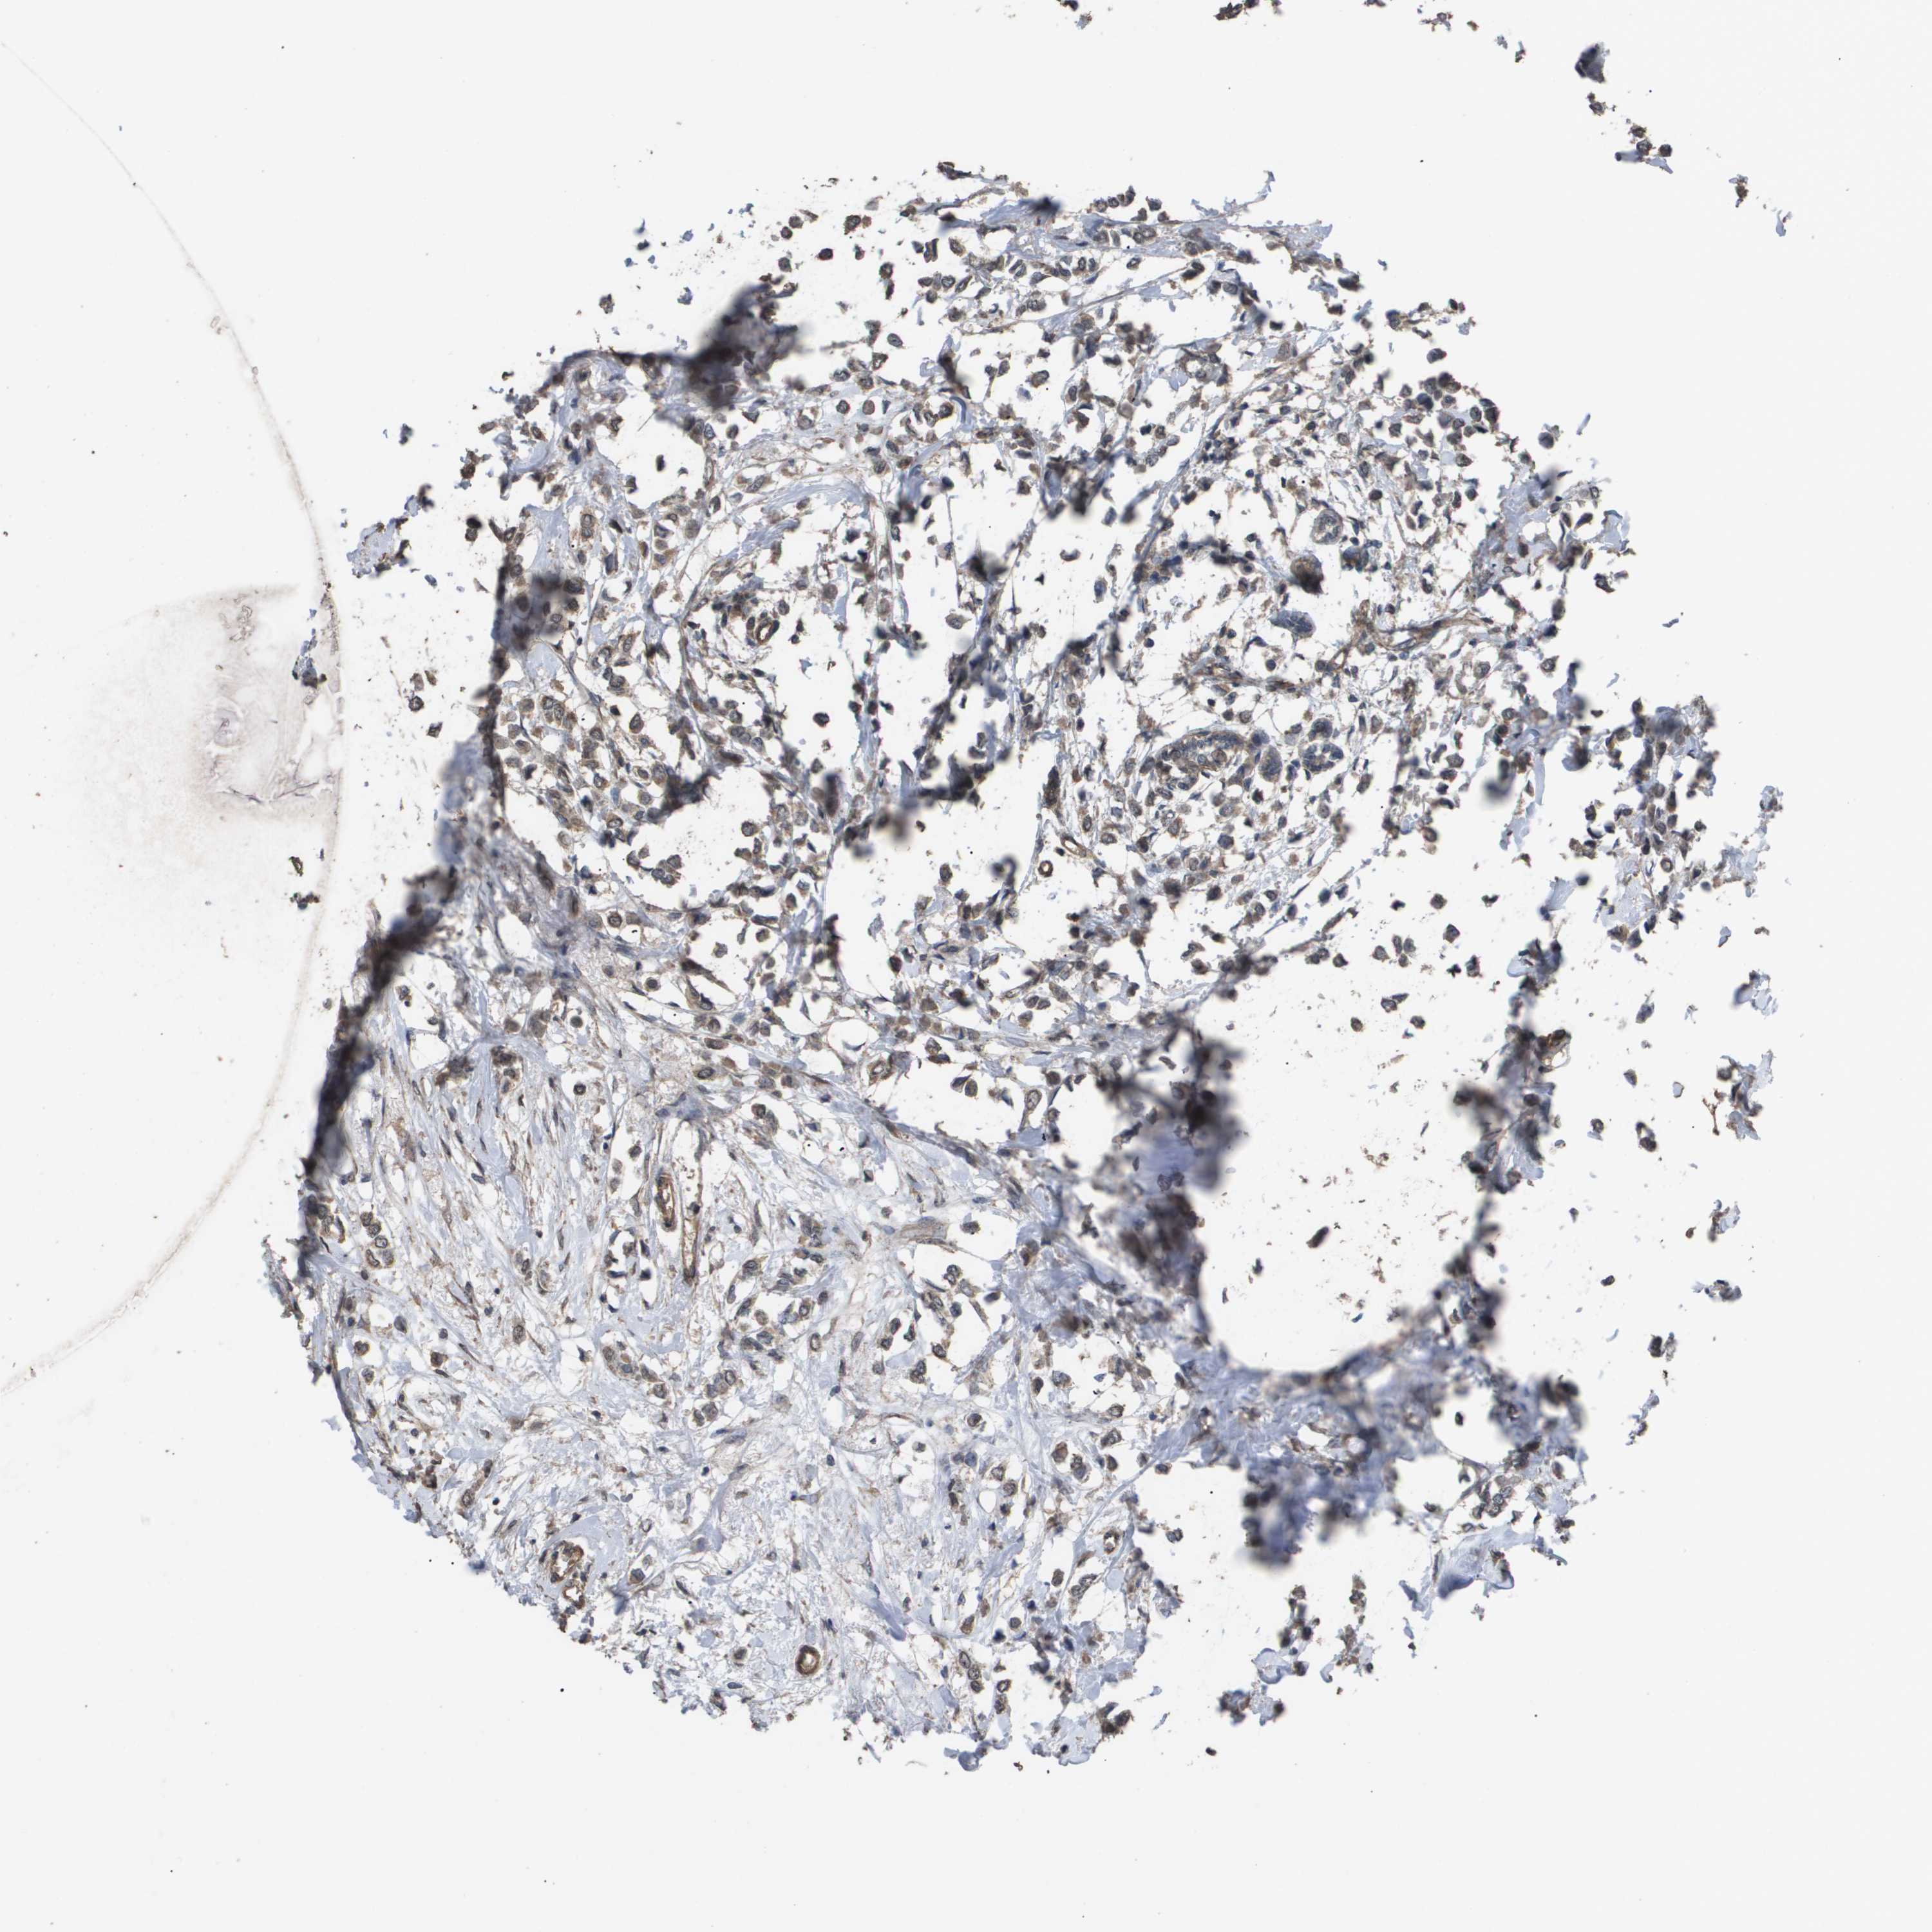

BRCA TCGA BRCA VALIDATION PROTEIN EXPRESSION

ANTIBODIES

AND

VALIDATION